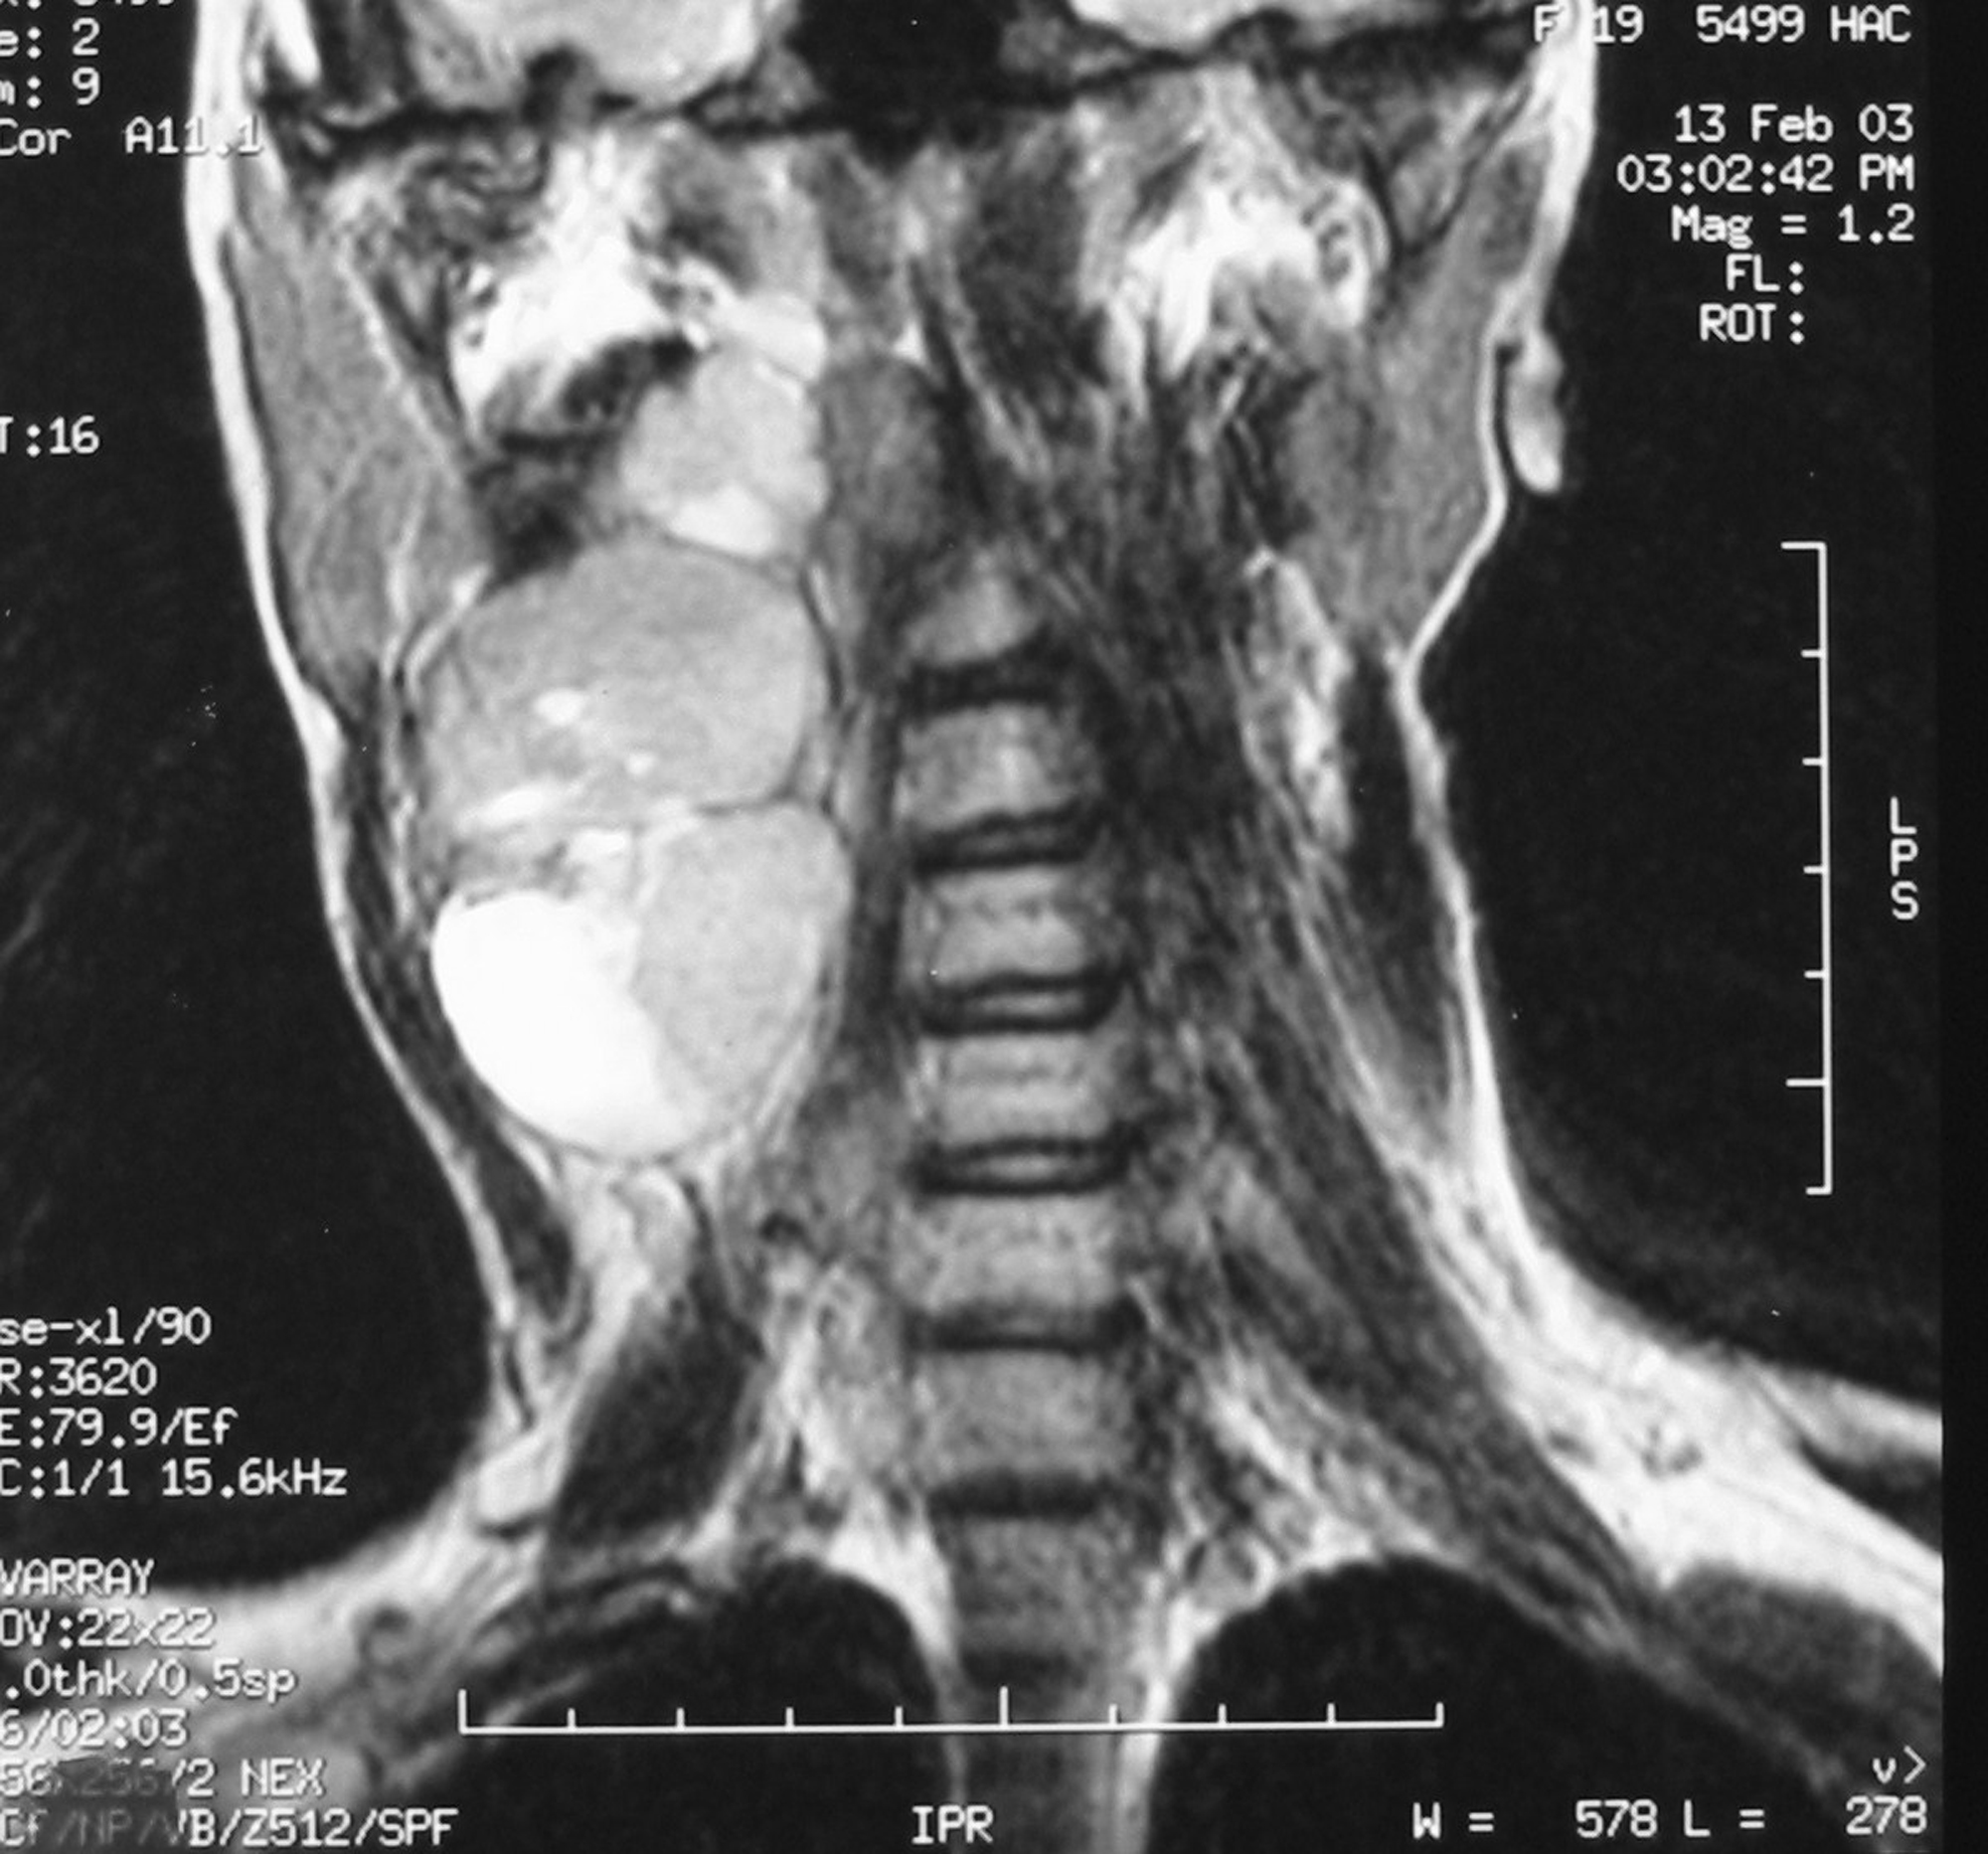

There were 6 females and 6 males (sex ratio 1 : 1) ranging in age from 6 to 47 years (mean age: 21 years). Eight cases occurred in patients less than 20 years of age. The tumors occurred predominantly in the lower extremity (10 cases: foot in 4 cases, thigh in 4 cases and calf in 2 cases), one case arose in the upper extremity (elbow) and one case in the hypopharynx. The primary presenting symptoms comprised a painful tumefaction in 6 cases, isolated pain in 3 cases, dysphagia in the case of oropharyngeal SS and cough and expectorations in one case of SS revealed by lung metastasis. In the remaining case, SS was revealed by traumatism of the affected area. The mean time from onset of symptomatology and pathological diagnosis of sarcoma ranged from 2 months to 6 years. Clinical examination showed a painful tumefaction, firm in consistency, fixed to the deep plan, without cutaneous signs. Standard radiographs of the tumors were made in all the cases and showed calcifications in 2 cases, a well defined opacity in 3 cases, bone invasion in 4 cases and were interpreted as normal in 3 cases. Echography, performed in 6 cases, was assessed as normal in 6 cases and showed a heterogeneous mass in one case and a hypoechoic mass in one case. Computed tomography studies were undertaken at the first presentation in 7 cases and showed a heterogeneous mass with heterogeneous vascular enhancement (Fig. 1), invading adjacent bone in one case; calcifications were observed in 2 cases and the diagnosis of SS was suspected in one case. Magnetic Resonance Imaging (MRI) examination was performed primarily in 3 cases and showed a well defined mass enhancing asymmetrically after gadolinium injection (Fig. 2). The neoplasms were hypointense on T1-weighted MR images and hyperintense on T2-weighted MR images, vascular invasion was seen in one case and the diagnosis of SS was suspected in one case.

![]() Click for large image | Figure 2. Coronal T2-weighted MR image showing a laterocevical tumor with heterogeneous signal. |